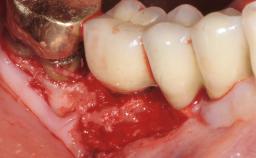

In this case, Myroslav Solonko, Ignacio Sanz Sánchez and Mariano Sanz present a treatment that aims to eliminate exposed implant threads by modifying the implant surface, converting a moderately-rough surface into a smooth surface.

A 63-year-old male patient was referred to the post-graduate periodontal clinic of the Complutense University of Madrid for the treatment of peri-implantitis. According to the patient’s record, all his maxillary teeth had been extracted ten years previously due to severe periodontitis, and a full-mouth implant-supported restoration on eight implants was placed. No supportive periodontal therapy was provided apart from occasional check-ups by the restorative dentist.